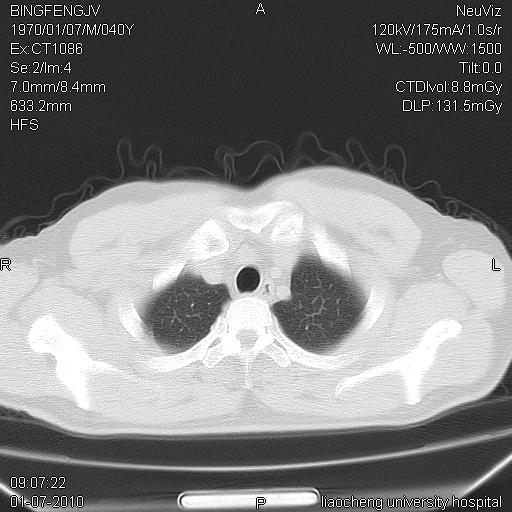

炎症性病灶,继发性改变。

考虑左肺上叶近胸膜下炎症并肺气囊形成。

炎症,大部吸收。